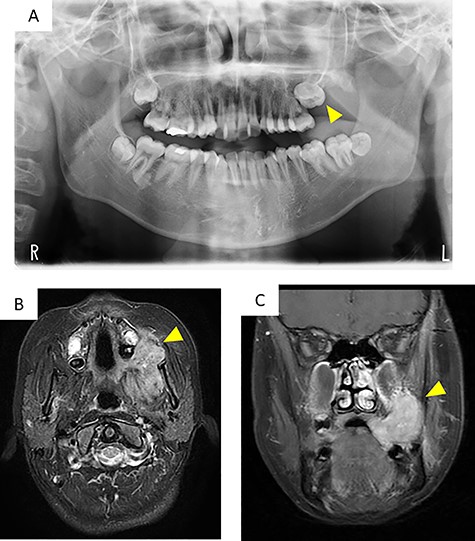

Panoramic radiography showed impaction of the left maxillary second molar and resorption of alveolar bone between the left maxillary molar area and the maxillary tuberosity (Fig. 2A).

Imaging findings; (A) a panoramic radiograph showing impaction of the maxillary second molar and resorption of alveolar bone between the left maxillary molar area and the maxillary tuberosity (arrowhead); (B and C) contrast-enhanced T-1 weighted MRI showing a high signal in the mass extending from the left masticator space to the buccal space and the maxillary and mandibular alveolar regions (arrowhead)

Computed tomography (CT) images showed a mass that extended from the left masticator space to the buccal space and the alveolar regions of the maxilla and mandible and pressure resorption of the anterior border of ramus, rear wall of the maxillary sinus and lateral plate of the pterygoid process. Involvement of the maxillary sinus was also suspected. Contrast-enhanced T1-weighted magnetic resonance imaging (MRI) showed a high signal in a range similar to CT (Fig. 2B and C). Contrast-enhanced effects in the left cervical and retropharyngeal (Rouviere) lymph nodes were also detected. 18F-fluorodeoxyglucose (18FDG)-positron emission tomography/CT showed a mass measuring 63 × 38 × 45 mm (long axis × minor axis × height) located in the left maxillary gingiva, accompanied by abnormal accumulation of 18FDG (standardized uptake value [SUV] max, 8.3), and left cervical lymphadenopathy, accompanied by abnormal accumulation of 18FDG (SUVmax, 41.72), which was suspected as metastasis. Abnormal accumulation was not observed in the other organs.